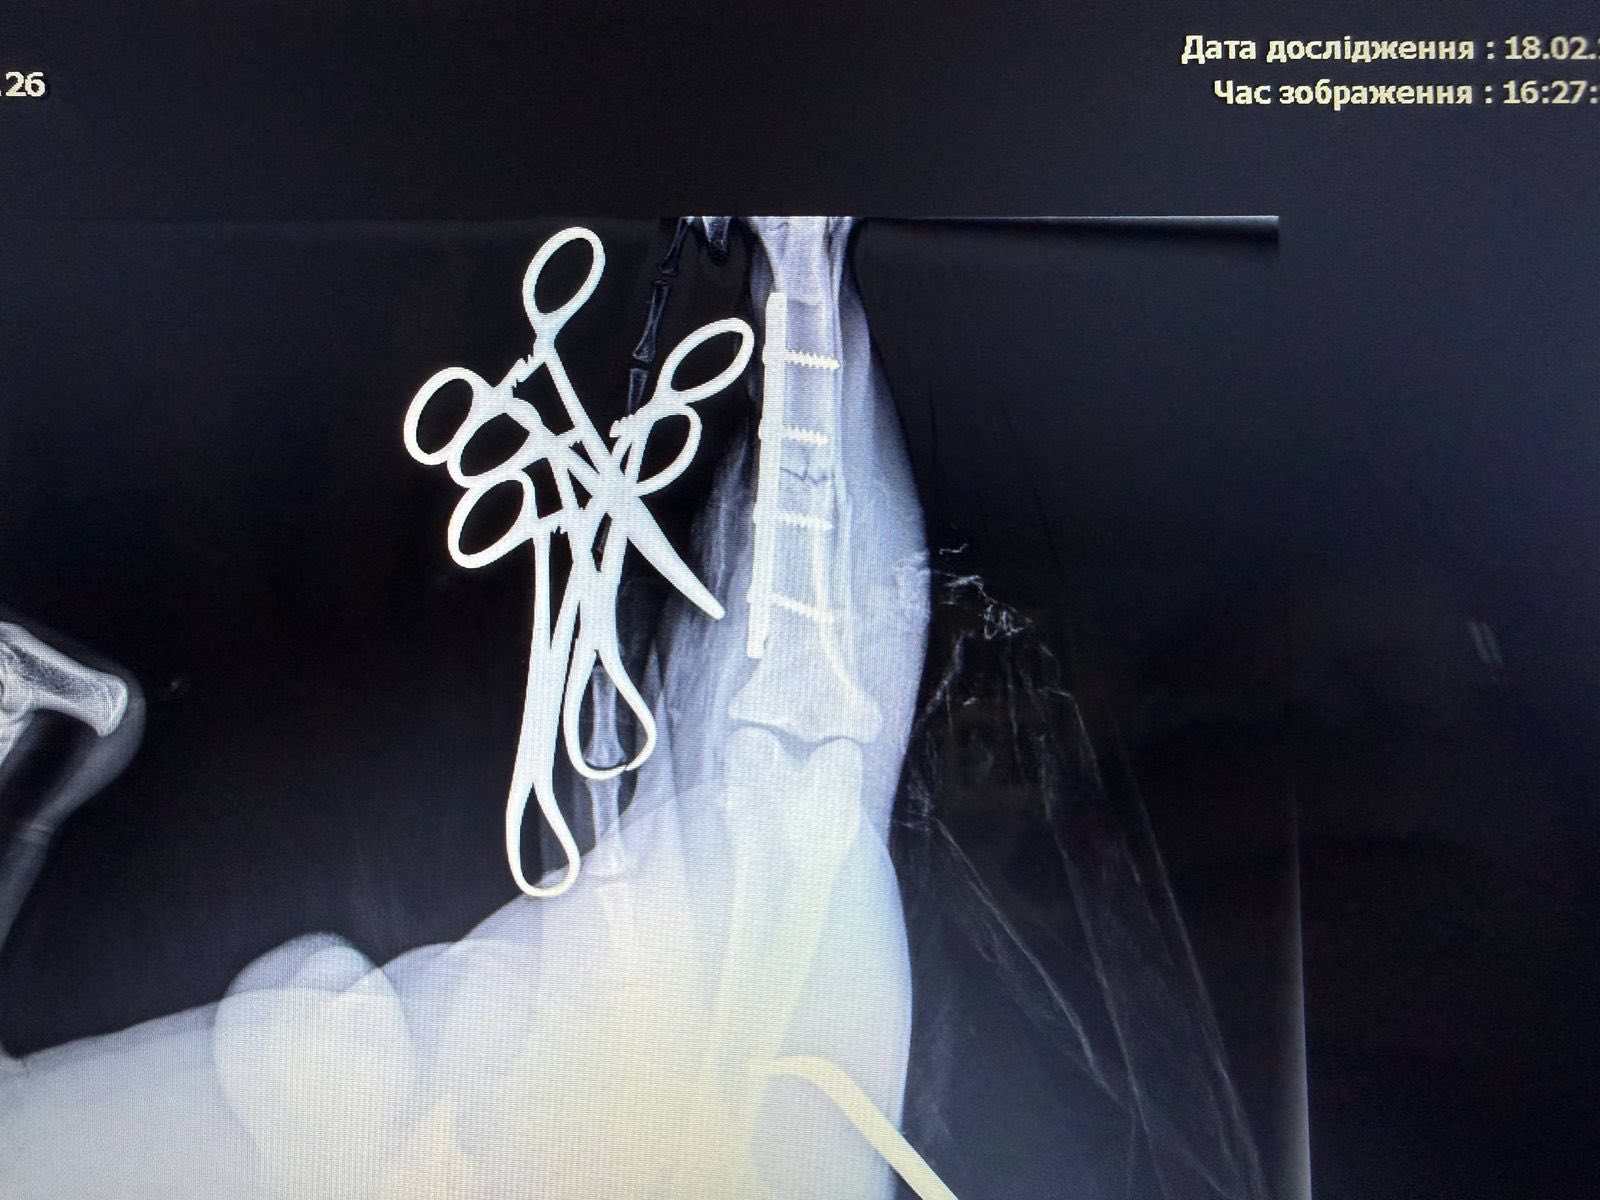

После осмотра врачи установили перелом голени задней лапы.

Ветеринары провели срочную операцию, которая прошла успешно.